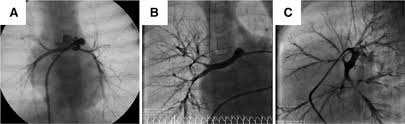

Demonstration Of Peripheral Pulmonary Stenosis And Supravalvular Aortic Stenosis By Different Cardiac Imaging Modalities In A Patient With Williams Syndrome Usefulness Of Noninvasive Imaging Studies International Journal Of Cardiology

Congenital Lvot Obstruction Seoul National University Hospital Department